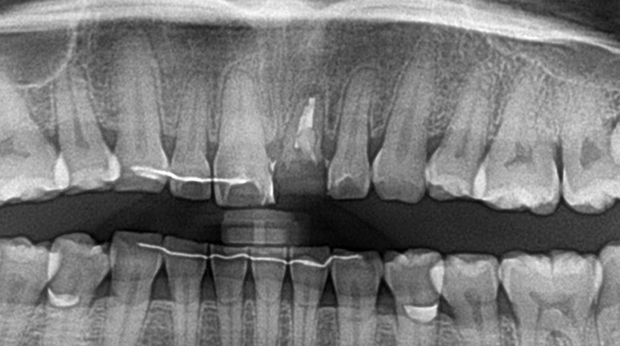

구강외과 진료

매복 사랑니 발치

임플란트와 사랑니 발치는 외과적 시술로 잇몸을 절개하는 외과적 시술은

짧으면 짧을 수록 시술 후 붓기와 통증이 최소화됩니다.

치과의사 경력 14년차 구강외과 전문의가 빠르고 안전하게, 아프지 않게 수술해 드립니다.